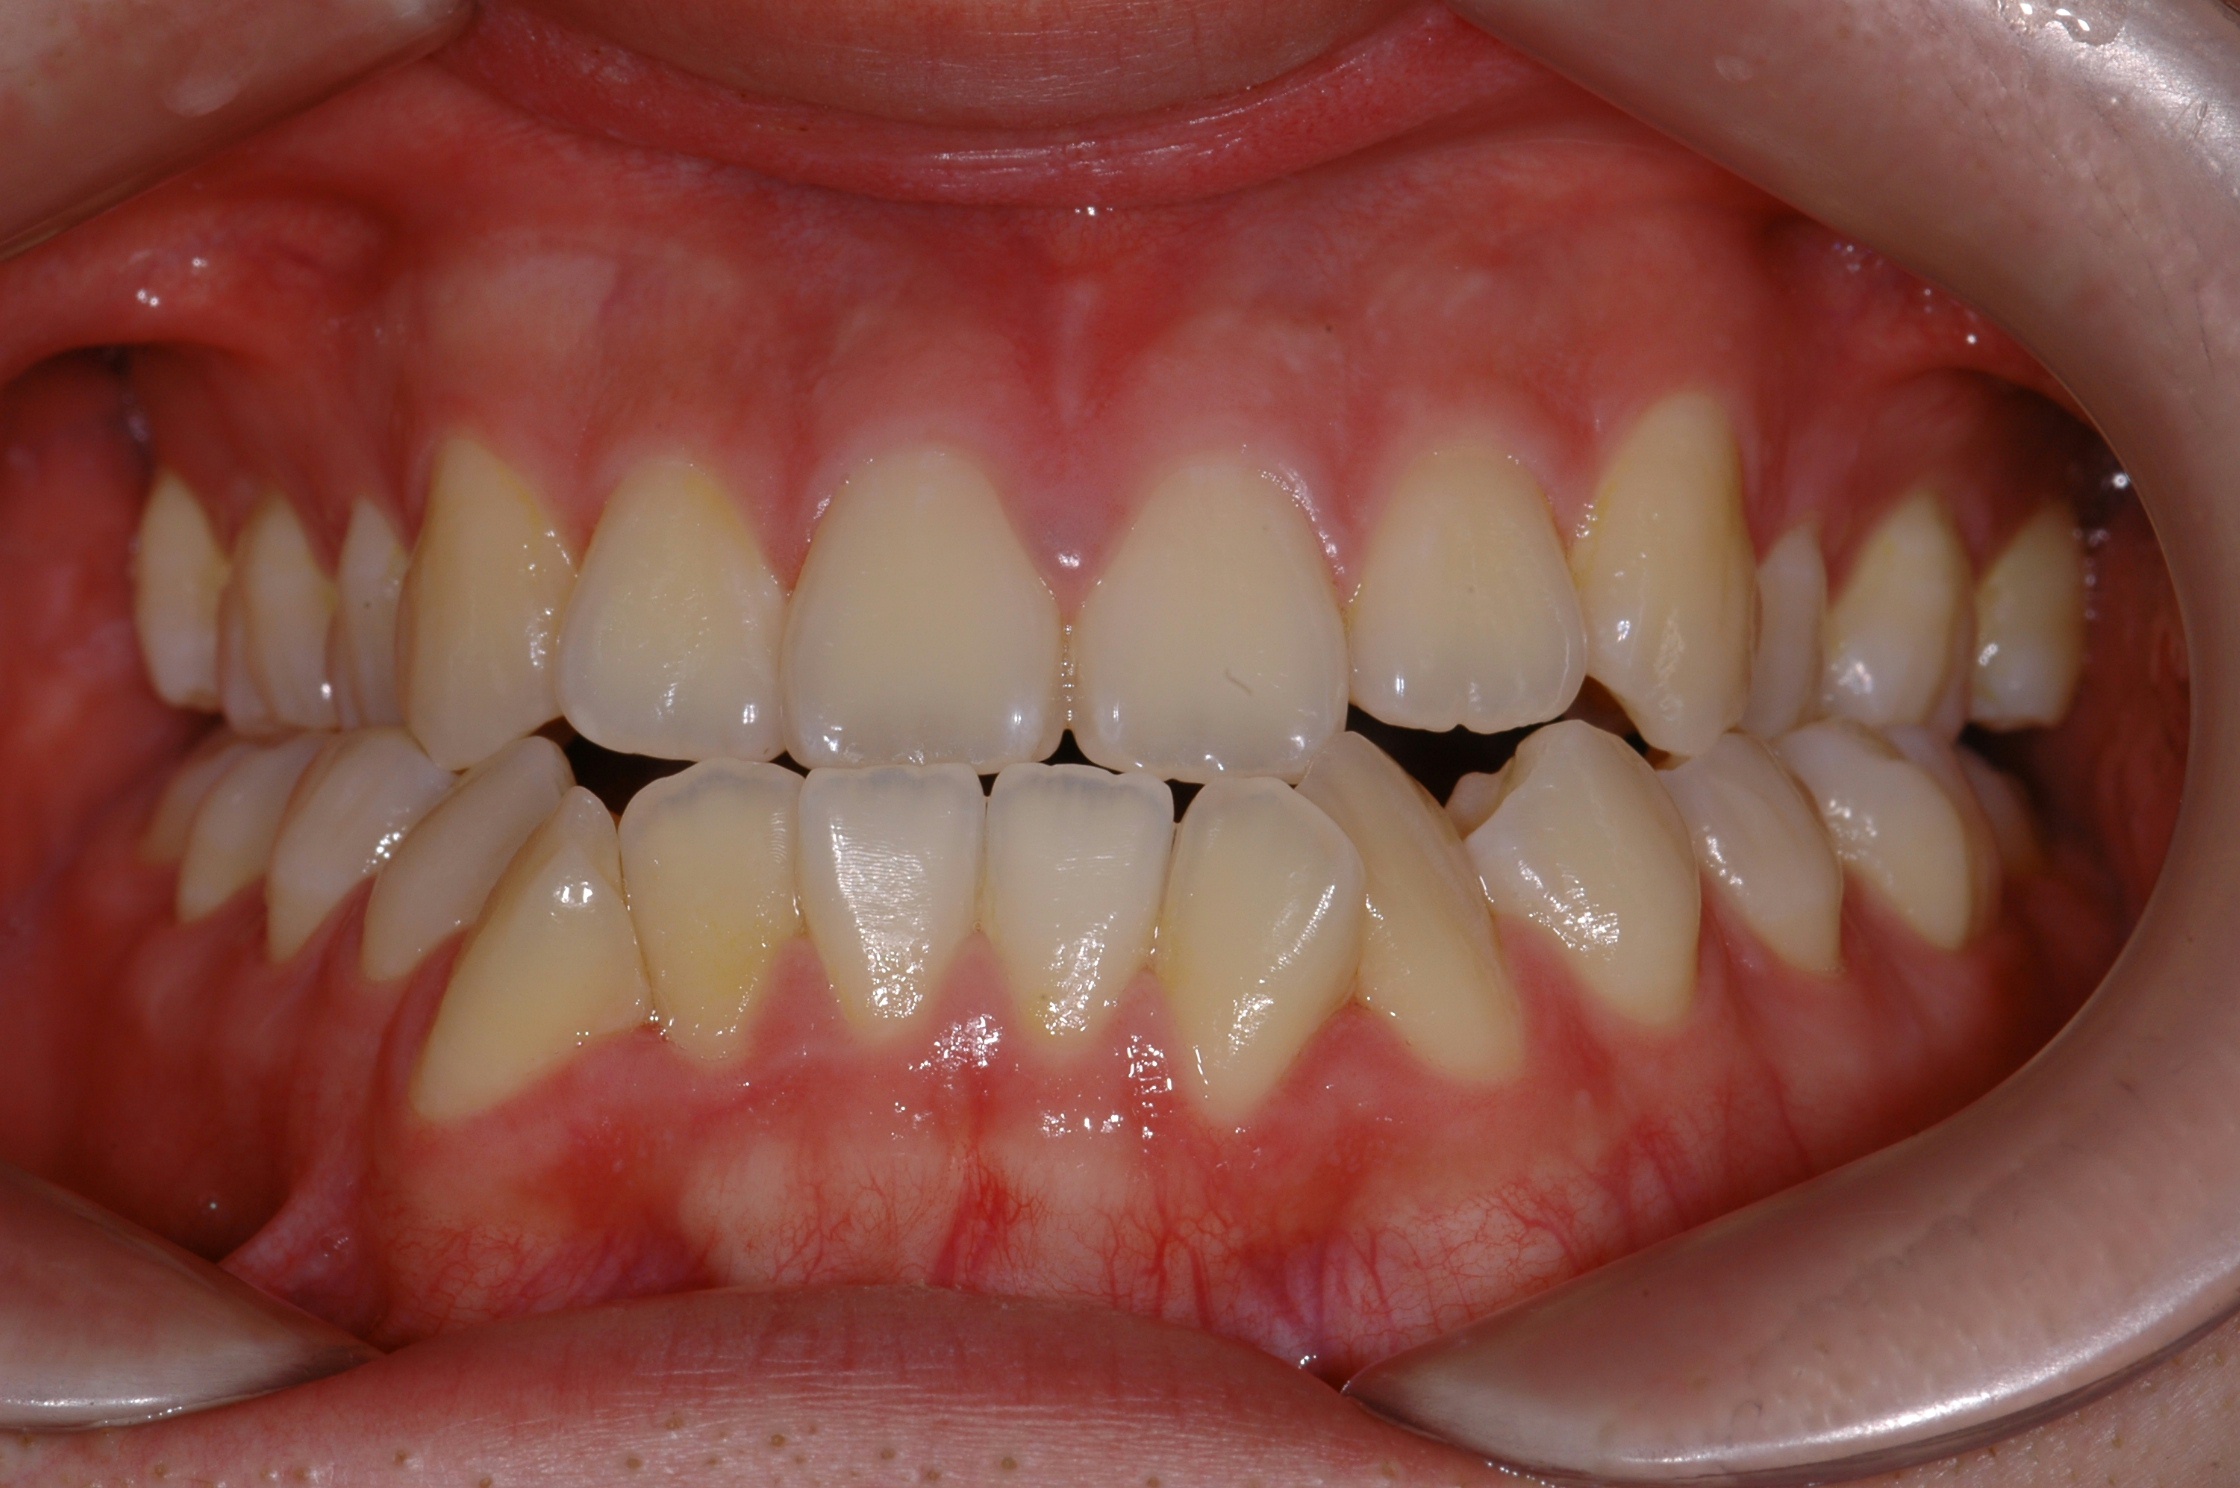

치료 전 사진입니다.